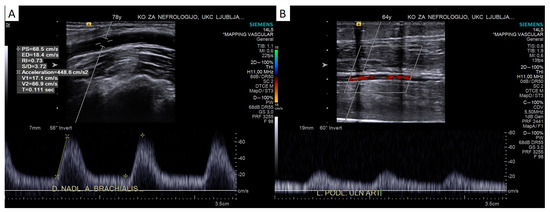

4.2.2. Pulsed-Wave Doppler Assessment

Peak Systolic Velocity

Doppler Curve Assessment, Acceleration Parameters

Reactive Hyperemia Test